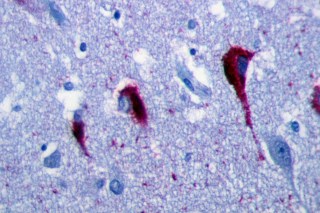

| Alzheimer’s patients often have neurofibrillary tangles caused by build-up of tau proteins. Image via Wikimedia Commons |

The research team focused on understanding how a group of proteins called tau proteins operate in cells. Diseases caused by problems with tau proteins are grouped together in a category called “tauopathies,” the most famous of which is Alzheimer’s Disease. One defining characteristic of tauopathies is that neurons have an unhealthy build-up of tau, which scientists think leads to neuron deterioration over long periods. A genetic mutation has been identified which predisposes people to this build-up of tau protein. Efforts to understand the deterioration tau causes have been stymied by the fact that it’s nearly impossible to observe neurons in action.